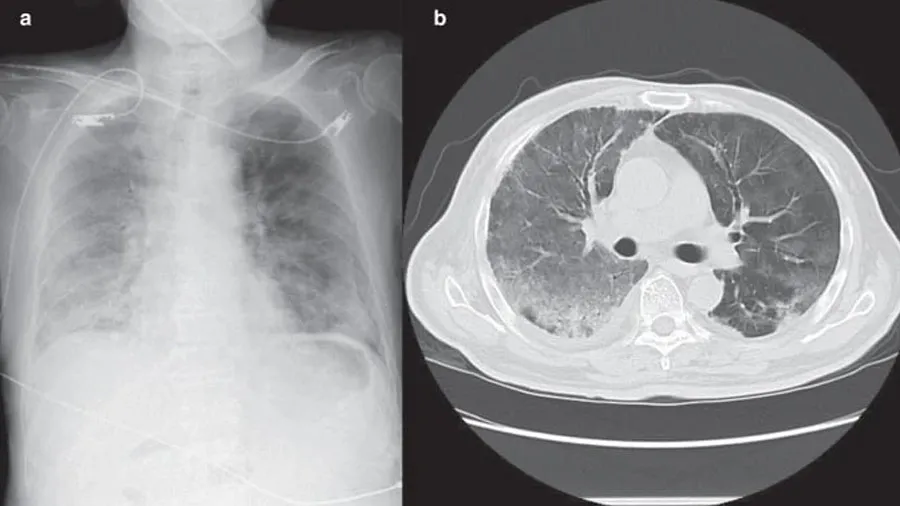

ચીનના નેશનલ હેલ્થ કમિશનમાં મેડિકલ પોલિસી અને એડમિનિસ્ટ્રેશનના ડેપ્યુટી હેડ જિયાઓ યાહુઈ કહે છે કે વ્હાઇટ લંગ્સ એ ન્યુમોનિયાનું વધુ ગંભીર સ્વરૂપ છે, જેમાં સફેદ ઈમેજ એરિયા દર્દીના ફેફસાના 70 થી 80 ટકા સુધી પહોંચે છે. તેમણે એમ પણ કહ્યું કે આવા લક્ષણો ધરાવતા દર્દીઓનું પ્રમાણ ખરેખર ઘણું ઓછું છે.

ચીનમાં કોરોનાનો પ્રકોપ હજુ યથાવત છે. ICU દર્દીઓથી ખીચોખીચ છે, ચીનની સરકાર દિવસ રાત દવાઓનું ઉત્પાદન કરીને દવાની અછત દુર કરવામાં લાગેલી છે.સરકારે આઇબુપ્રોફેન અને Acetaminophen જેવી દવાઓનું ઉત્પાદન 4 ગણું વધારી દીધું છે. પરંતુ કોરોના સામે જંગના મોર્ચા પર ચીનની મુસીબત ઘટવાનું નામ નથી લઇ રહી. દર્દીઓના સીટી સ્કેનમાં વ્હાઇટ લંગ્સના રૂપમાં ચીન સામે નવો પડકાર આવીને ઉભો રહ્યો છે.

ચીનના તબીબોનું કહેવું છે કે ન્યુમોનિયાની શરૂઆત ખાંસી અને શરદી જેવા કોવિડ-19 લક્ષણોની સરખામણીએ 6થી 7 દિવસ પછી થઇ શકે છે. જો મોટી ઉંમરના દર્દીઓને શ્વાસ લેવામાં મુશ્કેલી હોય અથવા ઓક્સીજન લેવલ 93થી નીચે હોય તો તરત ડોકટર્સને બતાવવું સલાહ ભરેલું છે.